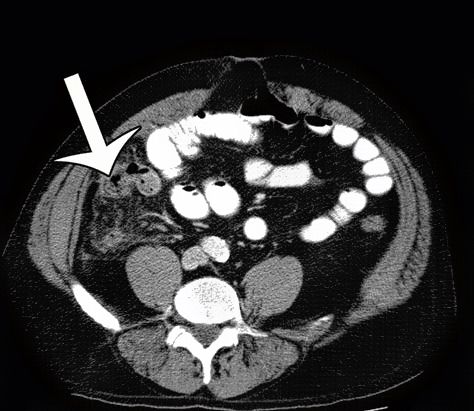

Η διάγνωση της οξείας σκωληκοειδίτιδας τίθεται ξεκάθαρα με την αξονική τομογραφία με χορήγηση σκιαγραφικών μέσων.

Συνεπώς με το που τεθεί η διάγνωση της οξείας σκωληκοειδίτιδας πρέπει να γίνει εισαγωγή σε χειρουργική κλινική και η πρώιμη εγχείρηση είναι απαραίτητη ούτως ώστε να αποφευχθούν οι σοβαρότατες επιπλοκές που σχετίζονται με τη ρήξη της (οξεία περιτονίτιδα).